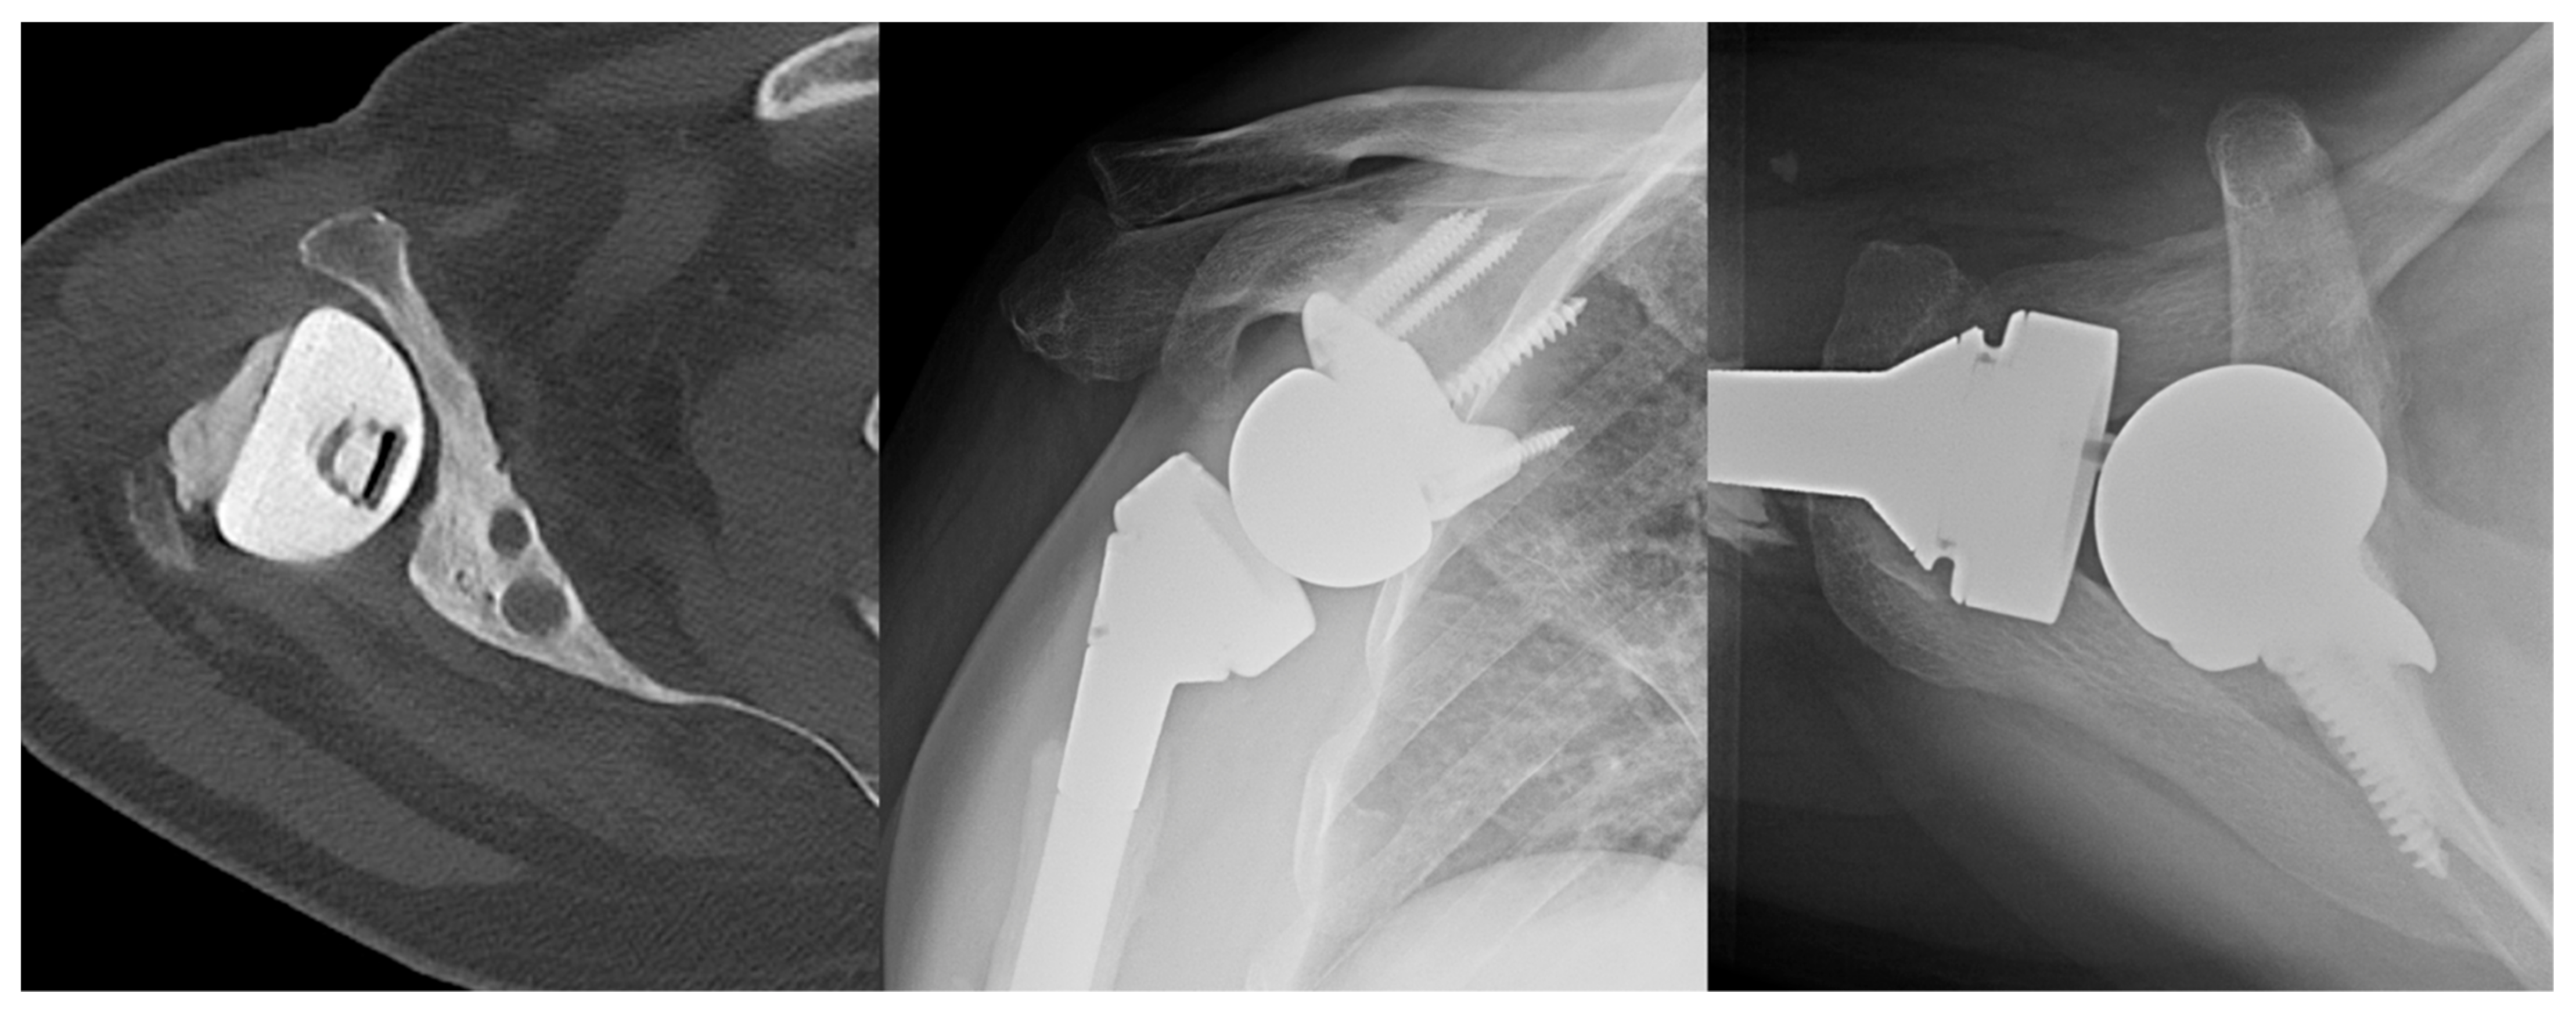

4. New Perspectives and Innovations in Revision Shoulder Arthroplasty and Complications

4.1. Convertible Implants

4.2. Humeral Bone Loss